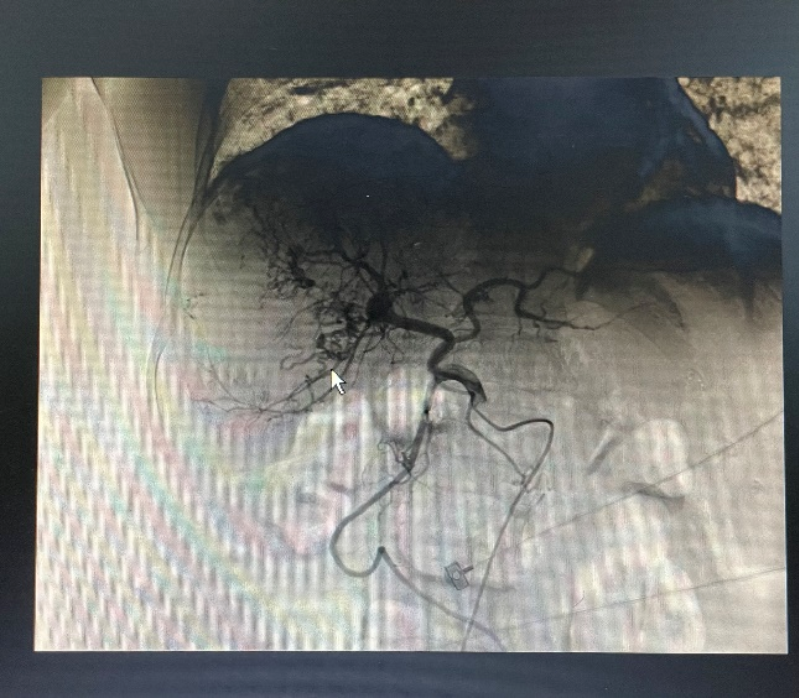

介入術中造影。

從影像中可以看出,之前因腫瘤直徑太大而無法切除,現通過介入灌注化療+靶向治療+免疫治療后,肝內病灶已基本無活性,后續可以進行手術切除腫瘤。